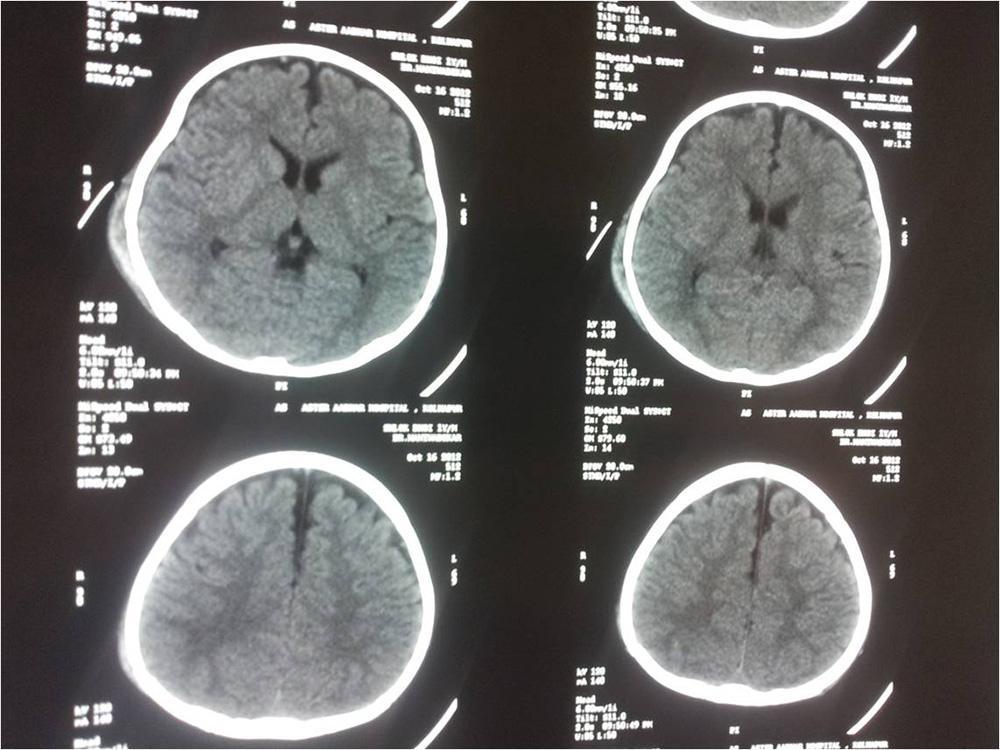

CT of Dai

• CT of Dai